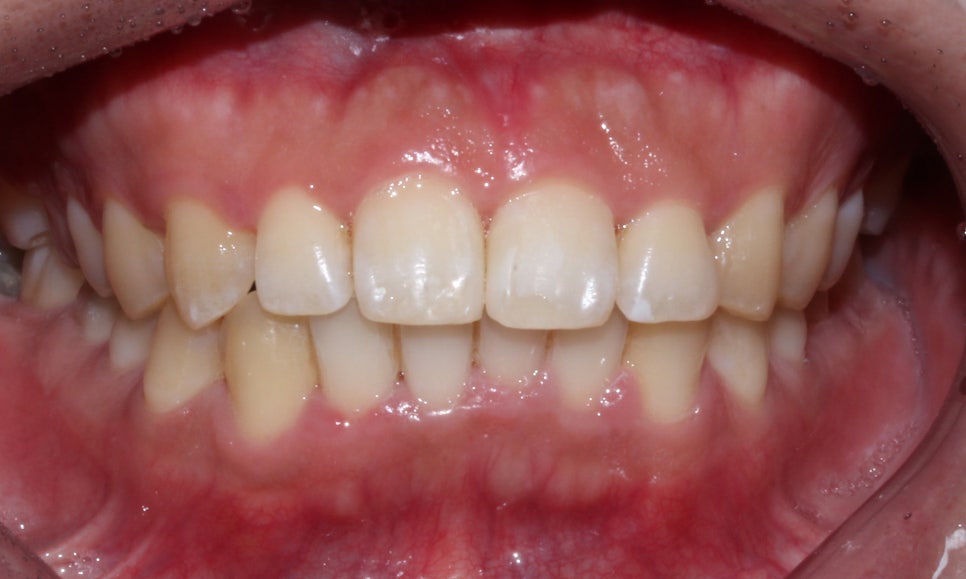

'뻐드렁니 교정 전(Before)'

뻐드렁니 부분교정 전

2D치과(투디치과)

뻐드렁니 교정 전 입술을 보시면

앞니의 돌출감으로 인해 입술이

튀어나와 있는 모습인데요,

앞니가 입술 방향으로 뻐드러져 있어

아랫니가 윗니에 많이 가려져 있는 모습입니다.

(+과개교합 증상이 보이는 모습이에요)

아랫니의 경우에는 삐뚤삐뚤한 치열로 인해

치아 사이에 치석이 많이 끼어있고 지저분한 모습입니다ㅠ0ㅠ

'뻐드렁니 교정 후(After)'

뻐드렁니 부분교정 후

뻐드렁니 교정 후 입술의 모습을 보시면

교정 전과 달리 입술에서 돌출감이 사라진 모습인데요,

아무래도 앞니가 둘어가다 보니 입술도 튀어나온 부분 없이

바르게 자리잡힌 모습입니다.

미소를 지었을 때 보이는 앞니 역시

뻐드렁니 교정 후 돌출된 부분 없이

깔끔하게 교정된 모습입니다~